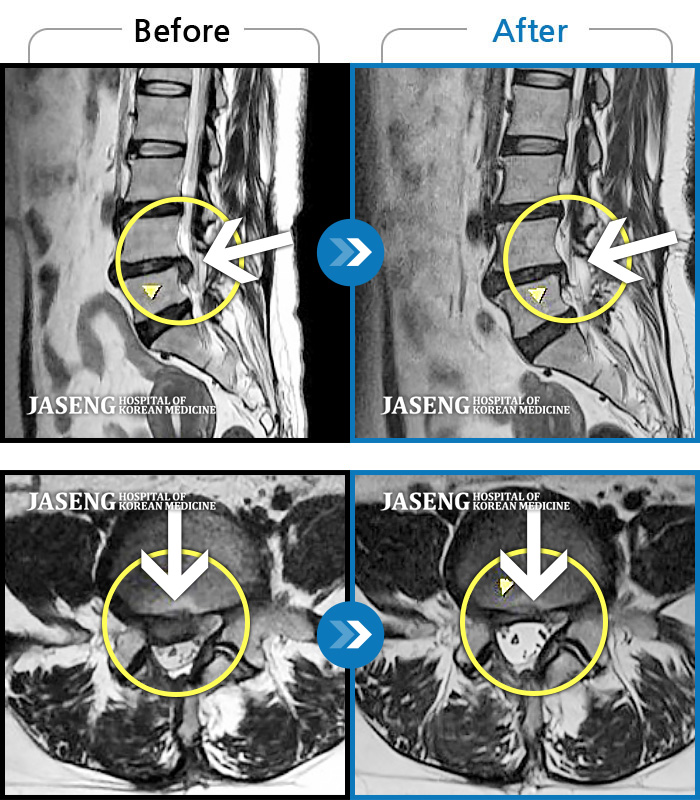

허리디스크

도움받은 사례

광주 · 장영우 원장

양측 허리의 묵직한 통증 및 기침 시 증상이 심화되어 내원하셨습니다.

촬영시기

2024.12.09 ~ 2025.05.24

2025.06.05